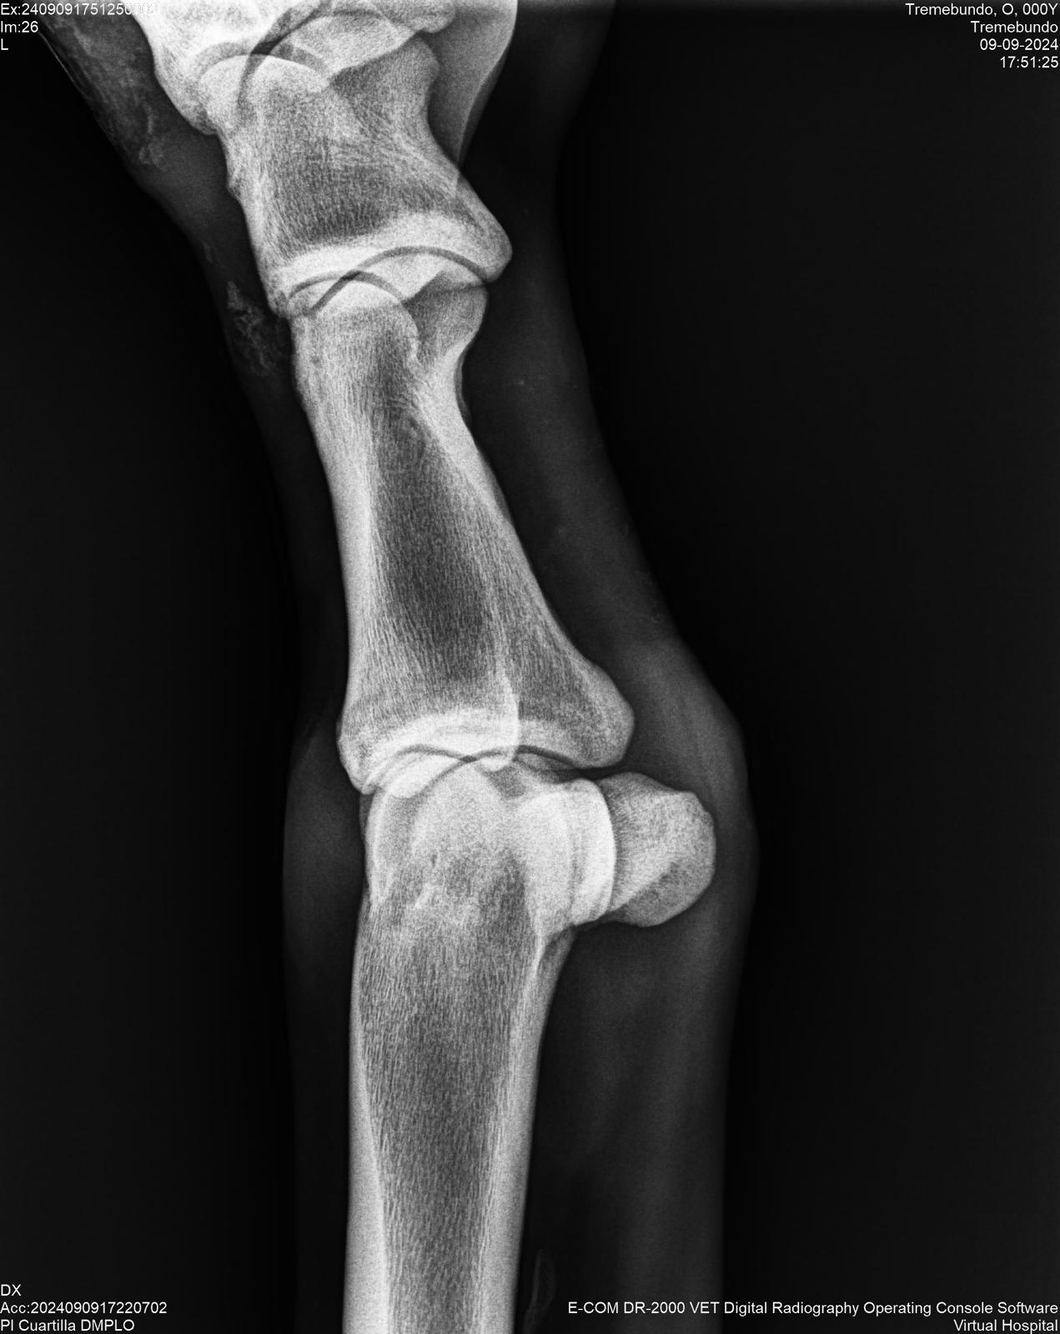

LOTE 37, TREMEBUNDO

Identificador: #291140-

Generacion 2022